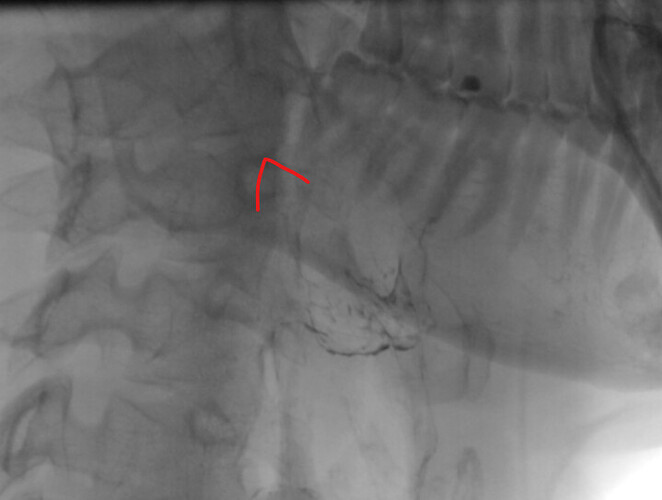

I also have some images from 2021 (taken during an investigation for dysphagia/pharyngeal pouch) which I think may show an elongated styloid. However, I’m not sure if I’m actually seeing something significant, or if it’s just artefact/normal anatomy.

I’ve also included a front-on image and highlighted around the bit that I think shows the styloid process. Is that it, or something else?